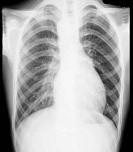

21岁男性患者,劳累后心悸、气促5年,听诊第2肋间有喷射性杂音,胸部三位片如图所示,你认为正确的描述和答案是 ( )A、考虑房间隔缺损B、...

问题 21岁男性患者,劳累后心悸、气促5年,听诊第2肋间有喷射性杂音,胸部三位片如图所示,你认为正确的描述和答案是 ( )

选项 A、考虑房间隔缺损 B、考虑室间隔缺损 C、右前斜位示左心房食管压迹未见明显加深 D、左、右前斜位示右心房段延长 E、后前位示心脏左移,主动脉结缩小,肺动脉段突出

答案 ACDE